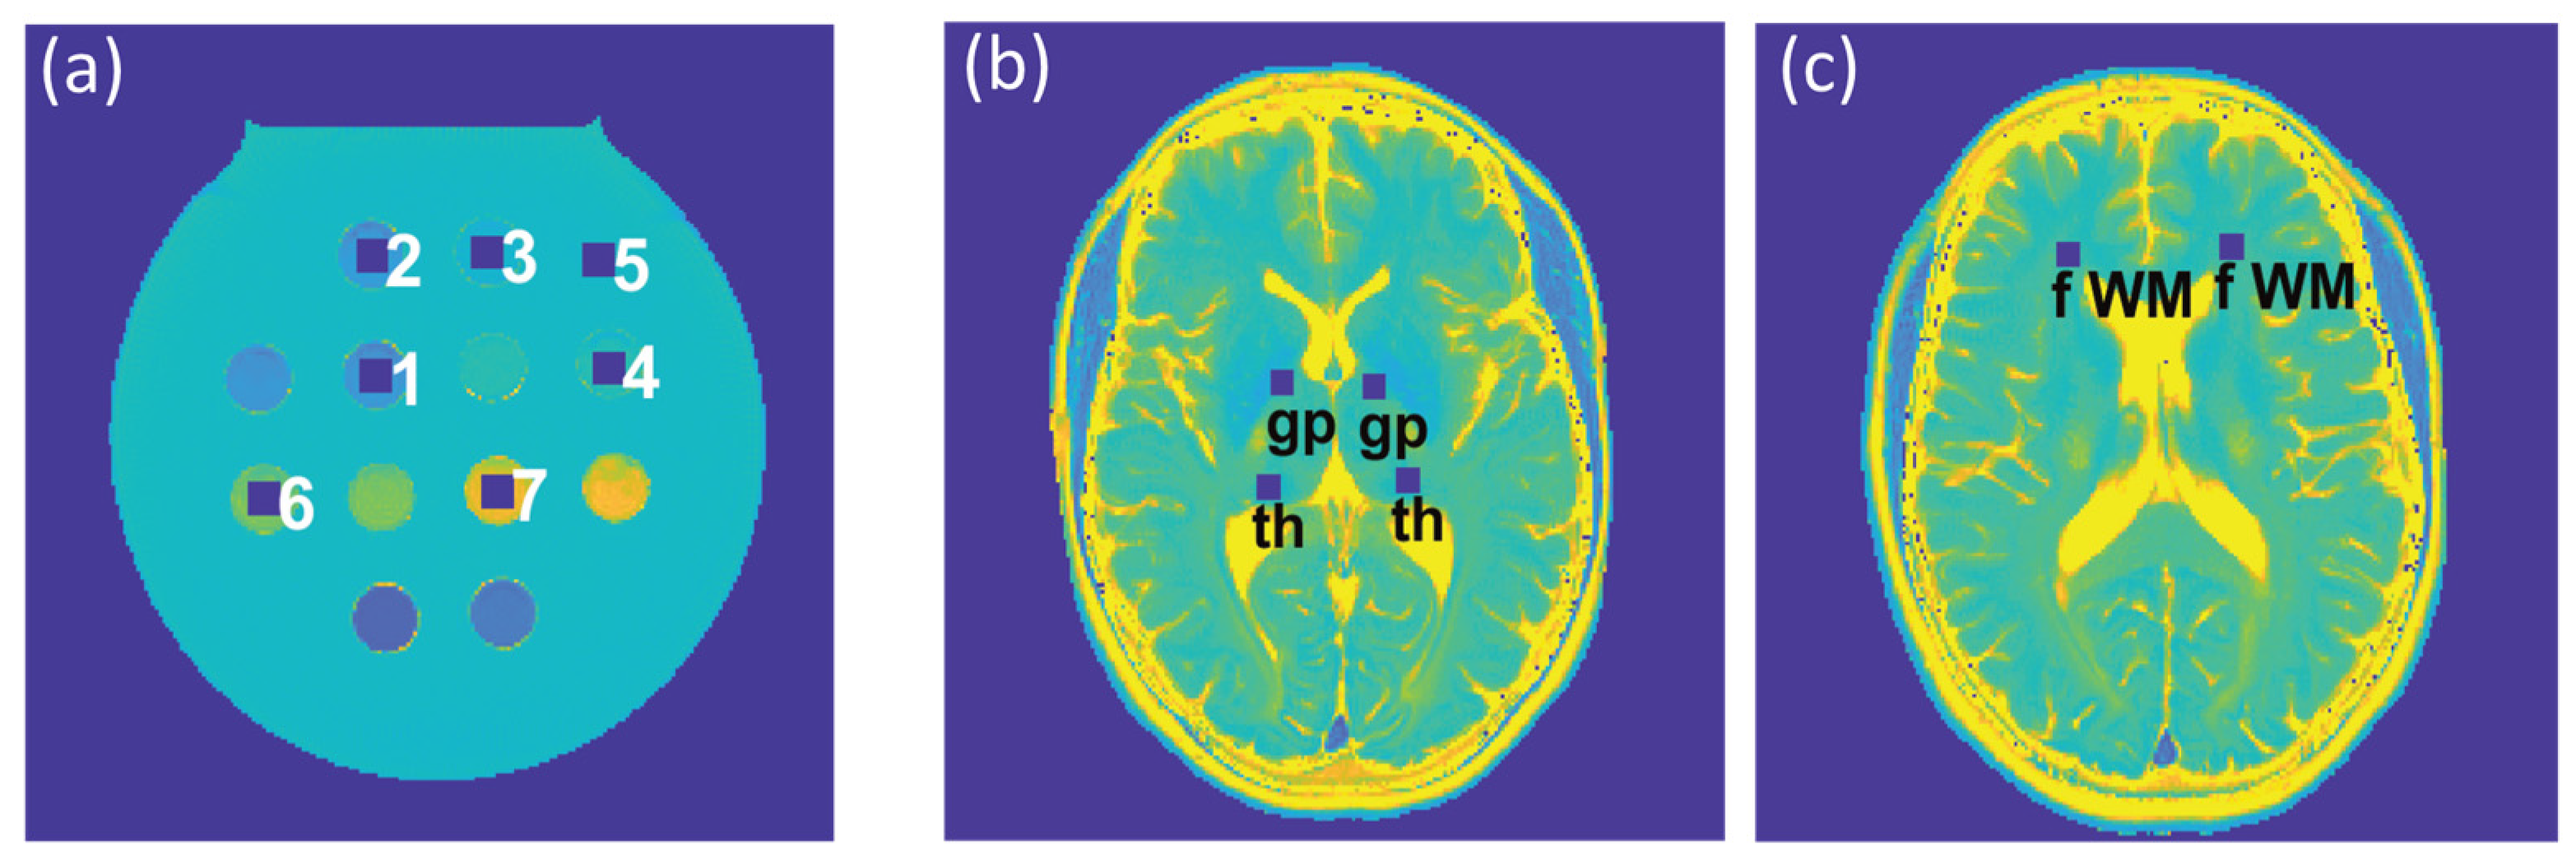

To assess the feasibility of undersampling, regression and Bland–Altman plot analyses were performed for every undersampling factor. T2 and T2* derived from CS-reconstruction of the undersampled data were benchmarked against T2 and T2* obtained from CS-reconstruction of the reference data (Rextra = 1). For analysis of the phantom study, seven ROIs (size = 9 × 9 pixels) were placed within the phantom (Figure 2a), corresponding to the position of the plastic tubes containing the varying iron concentrations. For analysis of the T2 and T2* maps obtained from healthy volunteers, six ROIs (size = 7 × 7 pixels) were selected for each subject, which were placed within the following anatomical brain regions: the globus pallidus, thalamus, and frontal (periventricular) white matter, in both, the left and right hemisphere (Figure 2b,c). For analysis of the T2 and T2* maps obtained from the patient cohort, eight ROIs (size = 7 × 7 pixels) were selected to cover MS lesions identified in four patients.

Figure 2.

(a) Regions of interest (ROIs) (size: 9 × 9 pixels), corresponding to tubes with varying iron concentrations in the phantom, which were used for the regression and Bland–Altman plot analyses and the calculation of the median absolute percentage error (MAPE). (b,c) ROIs (size: 7 × 7 pixels) used for further analysis of the in vivo study involving healthy volunteers were placed within the globus pallidus (gp) and thalamus (th) (b) and periventricular frontal white matter (fWM) (c), in the left and right hemispheres.